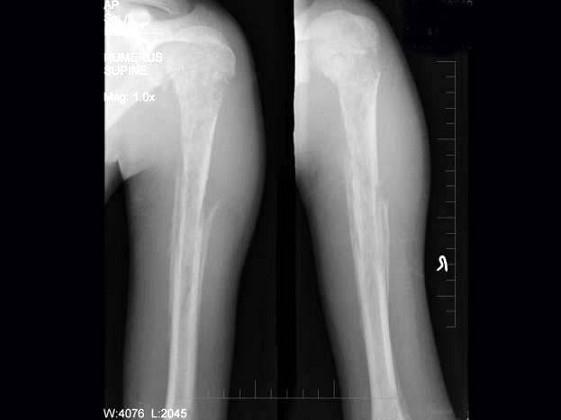

问题 男,15岁,畏寒,高热2周,摄片如图所示,下列描述正确的是?(?)

选项 A.骨质广泛性溶骨性破坏 B.少许骨质增生硬化 C.大量层状骨膜增生 D.以上描述均正确 E.以上描述均不正确

答案 D